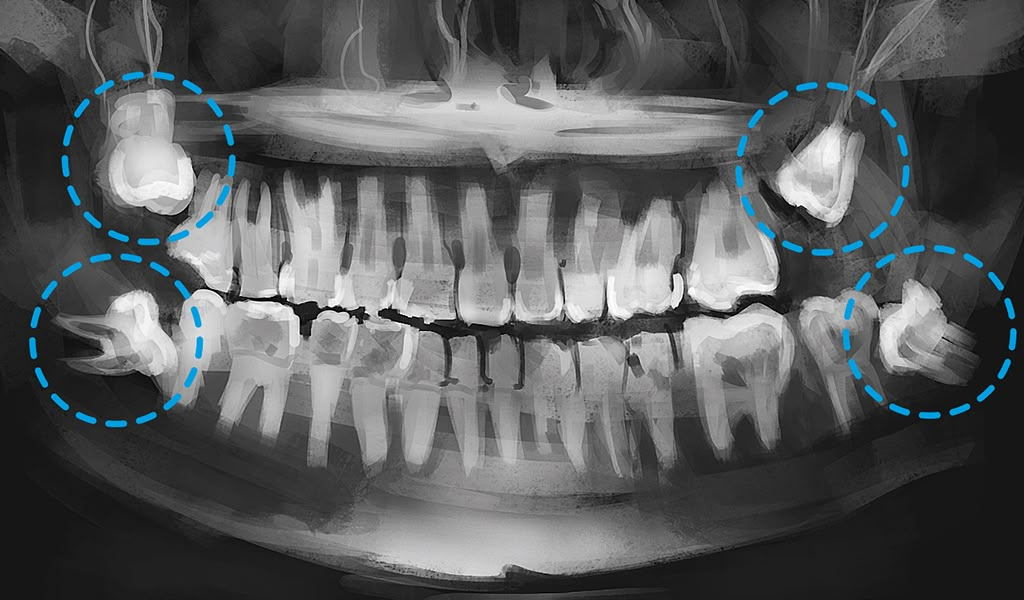

Răng khôn bị sâu là một trong những tình trạng răng miệng phổ biến nhưng dễ bị bỏ qua. Do nằm ở vị trí trong cùng của hàm, răng khôn thường sẽ khó vệ sinh. Dễ tích tụ các mảng bám và thức ăn thừa, từ đó tạo điều kiện cho vi khuẩn gây sâu răng phát triển. Nếu không được điều trị kịp thời, sâu răng khôn có thể dẫn đến nhiều biến chứng nguy hiểm.

Tại Sao Răng Khôn Dễ Bị Sâu?

Có nhiều yếu tố dẫn đến răng khôn dễ bị sâu hơn các răng khác:

👉 Vị trí nằm trong cùng hàm: Việc vệ sinh răng khôn khó khăn hơn do hạn chế tầm với của bàn chải hoặc chỉ nha khoa.

👉 Răng mọc lệch, mọc ngầm: Khi răng khôn không mọc thẳng, chúng tạo ra các khe hẹp dễ giữ thức ăn, và mảng bám.

👉 Vệ sinh không đúng cách: Thói quen vệ sinh răng miệng chưa đúng cách, sẽ làm tăng nguy cơ sâu răng khôn mà không hay biết.

👉 Thiếu không gian mọc răng: Gây chen chúc, tạo áp lực lên răng bên cạnh, làm tổn thương mô nướu và xương ổ răng.